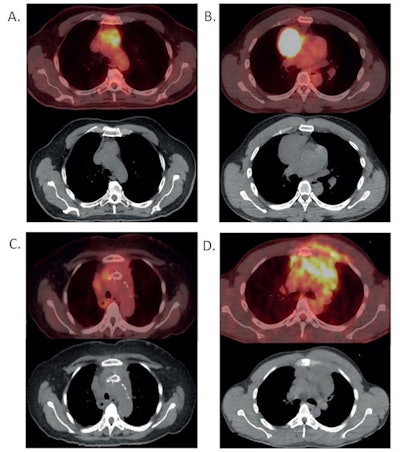

In this retrospective analysis, Byrd and colleagues aimed to determine whether F-18 FDG-PET/CT scans can differentiate between the thymoma and lymphoma without the need for biopsies, instead utilizing differences in maximum standardized uptake values (SUVmax) of the FDG radiotracer to distinguish between the two types.

The median SUVmax of thymoma and lymphoma differed dramatically, according to the findings: 4.35 for thymomas versus 18 for lymphomas (p < 0.001). An SUVmax < 12.85 was associated with thymoma with 100% sensitivity and approximately 89% positive predictive value, while SUVmax < 7.5 demonstrated 100% positive predictive value for thymoma.

In other words, tumors with SUVmax < 7.5 are likely thymoma and thus can be surgically removed without biopsy, while tumors with SUVmax > 7.5 should be biopsied to rule out lymphoma, the researchers suggested. Lymphoma is likely with SUVmax > 12.85, they added.